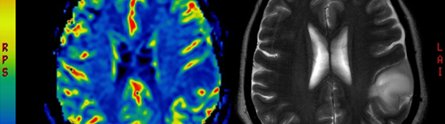

Brain scan